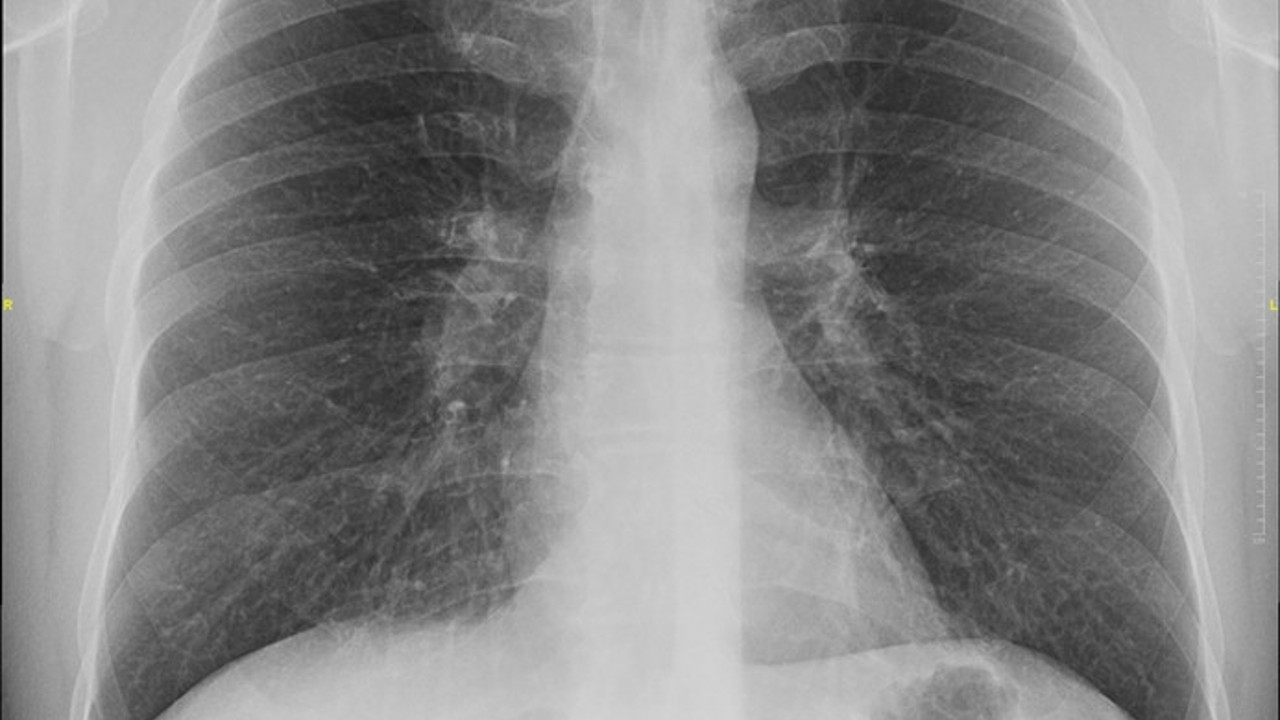

Sigarayı bırakmak, vücutta sandığınızdan çok daha hızlı ve fazla etkiye neden oluyor. Bıraktığınızdan iki saat sonra nikotin vücudu terk etmeye başlıyor. 12 saat sonra ise kandaki karbonmonoksit seviyesi normale dönüyor. Üç ay sonrasında da kalp krizi riski azalmaya, akciğer fonksiyonları artmaya başlıyor. Bu üç neden bile sigarayı hemen bırakmak için yeterince motive edici. Diğer yandan Türkiye’de Sağlık Bakanlığı, tiryakilerin bu alışkanlıktan kurtulmaları için önemli adımlar atıyor. Ülke çapında 400’den fazla Sigara Bırakma Polikliniği’nde tiryakilere ücretsiz ilaç desteği veriliyor.Türkiye Aile Hekimleri Uzmanlık Derneği (TAHUD) Başkan Yardımcısı ve Namık Kemal Üniversitesi Tıp Fakültesi Aile Hekimliği Anabilim Dalı Başkanı Prof. Dr. Dilek Toprak, tiryakilerin genellikle kendilerini sigarayı bırakmak için “yeni başlangıçlar takvimi” belirlediğini ve bunun de yılın ilk günleri olduğunu belirtiyor.

Bilimsel olarak etkinliği kanıtlanmış üç sigarayı bırakma yöntemi var: Terapötik yöntemler, davranışsal tedavi ve ilaç tedavisi. Bunların dışındaki hiçbir yol bilimsel olarak kanıtlanmamıştır ve kulaktan dolma öneriler işe yaramıyor ne yazık ki. Özellikle internetten ne olduğu bilinmeyen bitkiler ve macunlar sipariş etmek son derece tehlikeli olabilir. Bilimsel olarak henüz kanıtlanmamış, evrensel kabul görmemiş yöntemlere daima şüpheli bakın. Çünkü yan etkileri olabilir. Sigara bırakma polikliniklerinde çalışan hekimler tarafından yazılan ilaçlar devlet tarafından karşılanıyor. Bu polikliniklere başvurarak profesyonel destek alın ve bu bağımlılıktan kurtulun. Sigara içme isteği geldiğinde ortam değiştirme, ağzı çalkalama, diş fırçalama, salatalık havuç gibi düşük kalorili atıştırmalıklar yeme faydalı olur.